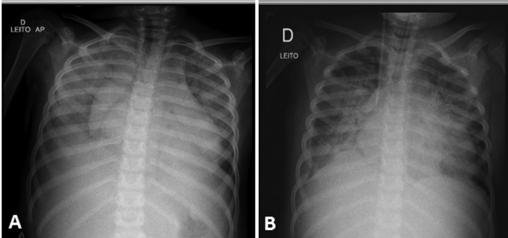

Paciente do sexo feminino, 4 anos e 8 meses, previamente hígida e eutrófica, sem vacinação prévia para vírus influenza. História de tosse e rinorreia há 2 semanas, com febre não aferida. Há 2 dias apresenta dor abdominal, vômitos e queda do estado geral. Admitida no pronto-socorro em mau estado geral, desidratada grave, normotensa, gemente, taquidispneica e taquicárdica. Temperatura: 38,1°C. Contagem de leucócitos: 10000/mm³, bastonetes 10/mm³, Frequência respiratoria: 36/min Tempo de enchimento capilar: 5 segundos.. Evoluiu com piora da taquidispneia, hipotensão, gemência, além de hepatomegalia, anasarca e presença de sopro cardíaco.

Exames laboratoriais evidenciaram anemia, acidose metabólica e elevação da concentração da proteína C-reativa. Eletrocardiograma evidenciou taquicardia sinusal (155 batimentos por minuto) e radiografia de tórax demonstrou aumento da área cardíaca, discreto derrame pleural à direita e infiltrado pulmonar difuso, sugestivo de congestão alveolar.

DISCUSSÂO: A reposição volêmica, de modo normal é de 20 ml/kg em 5-10 minutos. No entanto, cuidado com esse caso! Um coração aumentado na radiografia do tórax de uma criança com evidência de choque e débito cardíaco deficiente. Desse modo, neste caso não podemos administrar bolus de fluidos grandes ou rápidos. Preferencialmente, um bolus de fluido isotônico pequeno de 5 mL/kg a 10 mL/kg, com cautela e durante períodos relativamente mais longos (por exemplo, 10 a 20 minutos, em vez de 5 a 10 minutos) seria mais seguro. Os bolus grandes ou administrados muito rápido podem piorar a função cardíaca e aumentar o fluido já existente nos pulmões.